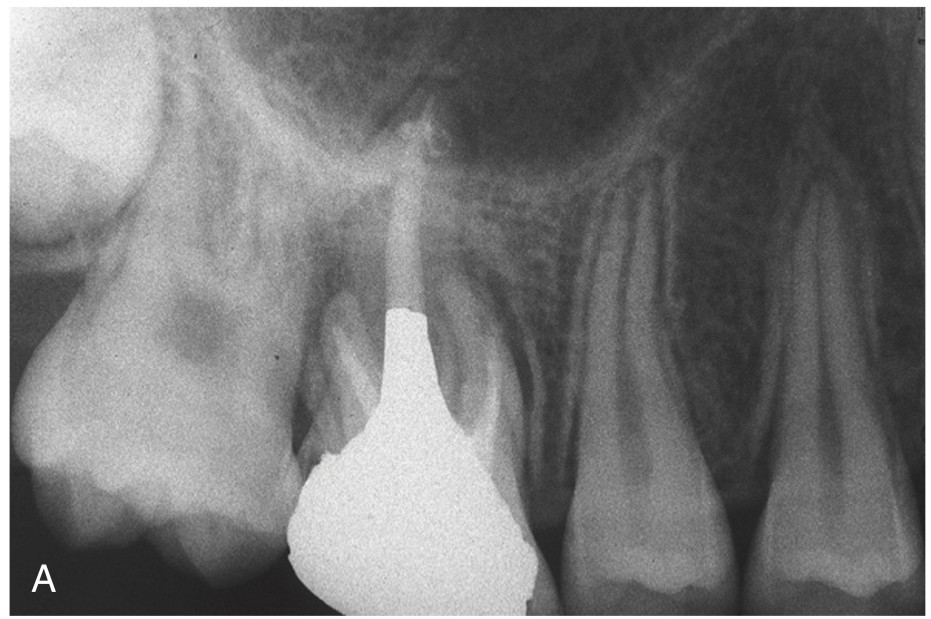

3. What option can describe the post placement in the X ray bellow for the tooth # 3.6?